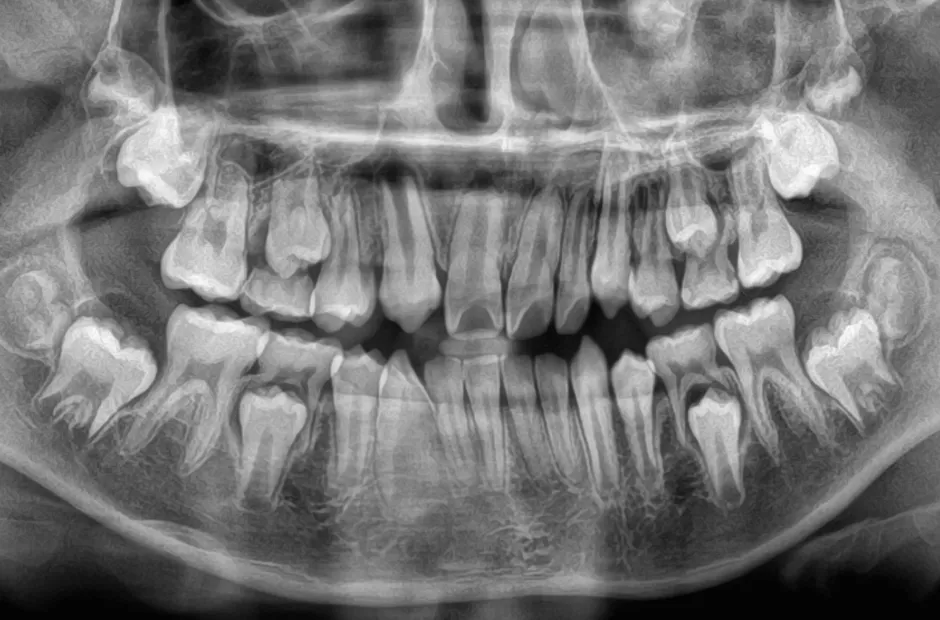

口腔内写真やレントゲンの撮影、歯型取りなど、口や顎の状態を詳しく把握するための精密検査を行ないます。さらに、骨の成長状況や身長・体重の増加傾向、永久歯の生えかわりについても確認します。

先天的な歯や顎の症状

永久歯が生えてこない(埋伏歯)

何らかの原因で永久歯が正常に生えることができず、歯肉に埋もれたままになる歯のことを埋伏歯といいます。この歯を放置すると、隣の歯根を吸収してしまうことがあるため、早めの治療が必要です。埋伏歯を早期に発見できると、抜歯せずに矯正治療で正常な位置に戻せる可能性が高くなります。これは、小児矯正では、顎の成長を促進して歯が正しく並ぶスペースを作ることができるからです。そのため、乳歯が永久歯に生え変わり始めるころに一度受診し、埋伏歯の有無を確認することが大切です。

永久歯の数が足りない

(先天性欠如)

先天的に永久歯が不足している状態を先天性欠如といいます。先天性欠如があると、すきっ歯になったり、乳歯が抜けずにそのまま残ったりすることがあります。すきっ歯の場合は、矯正治療ですき間を閉じることで、将来的にブリッジやインプラント、入れ歯が必要になる事態を回避できる可能性があります。歯科検診で指摘されるまで気づかれないことが多く、放置すると高確率で歯並びや噛み合わせに悪影響を及ぼします。調査によると、先天性欠如歯は10人に1人の割合で見られ、近年増加傾向にあります。

歯が多い(過剰歯)

通常、永久歯は親知らずを含めて32本ありますが、過剰歯とはその数を超えて余分に歯が生えている状態を指します。過剰歯が歯肉の中に埋まっていて、向きが悪くほかの歯に害を及ぼしている場合には抜歯が必要です。しかし、問題がなければそのまま経過を見守ることもあります。